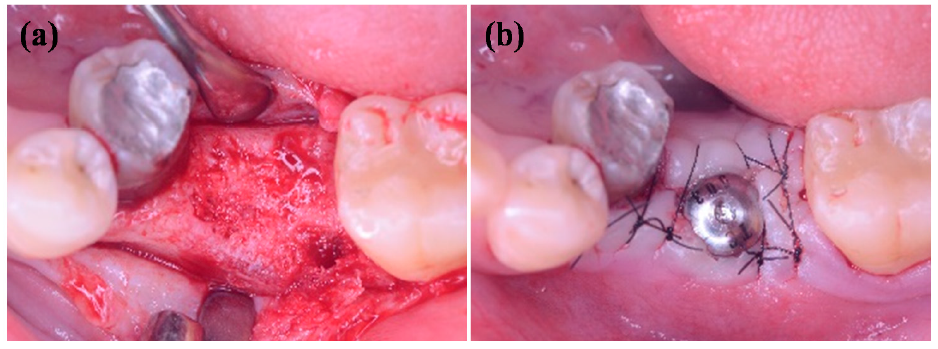

2.7. Radiograph Evaluations In Vivo

3.5. Radiograph Evaluations of the IDCT-Ti/GRGD-1 Implant